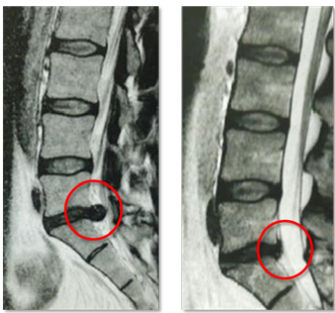

Die tiefliegenden Rückenmuskeln, oftmals auch als autochthon („ortsständig“) bezeichnet, haben eine Schlüsselfunktion bei der Aufrichtung und Stabilisierung der Wirbelsäule [Wagner et al., 2005]. Vor allem die Muskeln des sogenannten „medialen Stranges“ sind segmental angeordnet und daher für die segmentale Stabilisierung und Hauptkontrolle der Wirbelsäule verantwortlich (siehe Abb. 1) [Creze et al., 2015; Deng et al. 2015]. Unterstützt werden diese Muskeln von einem komplexen System aus Faszien. Gut trainierte Muskeln erhöhen diese fasziale Spannung und gewährleisten eine systemische Stabilität [Willard et al., 2012].